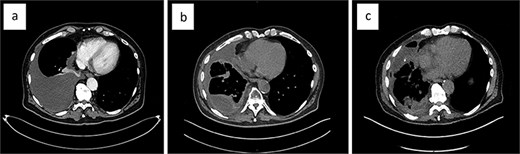

Systemic therapy with pazopanib 800 mg (2-0-0-0) was initiated early on. The patient experienced recurrent pleural effusions, which cytology confirmed contained EHE cells. The malignant pleural effusion (MPE) demonstrated rapid reaccumulation and was initially managed with repeat thoracenteses. During the first thoracentesis, 2000 ml of pleural fluid was aspirated. Sixteen days later, 2705 ml was drawn, and 1800 ml just 8 days later. Eventually, a video-assisted thoracoscopic surgery (VATS) was performed at another hospital, which included talc pleurodesis, achieving full lung re-expansion, and prophylactic indwelling pleural catheter (IPC) placement. Unfortunately, the patient continued to develop recurrent MPEs (Fig. 3a), now loculated and accompanied by lung entrapment (Fig. 3b), markedly increasing the complexity of management.

The evolution of the malignant pleural effusion over time. Progressively increasing pleural effusion ~4 months after first identified (a), a loculated pleural effusion after three repeat thoracocenteses, talc pleurodesis, and IPC placement (b); loculated pleural effusion about 2 months after VATS partial empyema evacuation (c).

The patient presented to our institution for further evaluation. We performed a VATS, achieving only partial evacuation of the empyema’s fibrinopurulent debris, due to excessive intraoperative bleeding (Fig. 3c). The histopathology of the visceral pleural fragments obtained showed no evidence of EHE. Two weeks later, we removed the chest drain with minimal effusion in the right costophrenic angle. The patient’s quality of life is still significantly reduced by his severe breathlessness, but after careful consideration, we decided against performing VATS decortication.